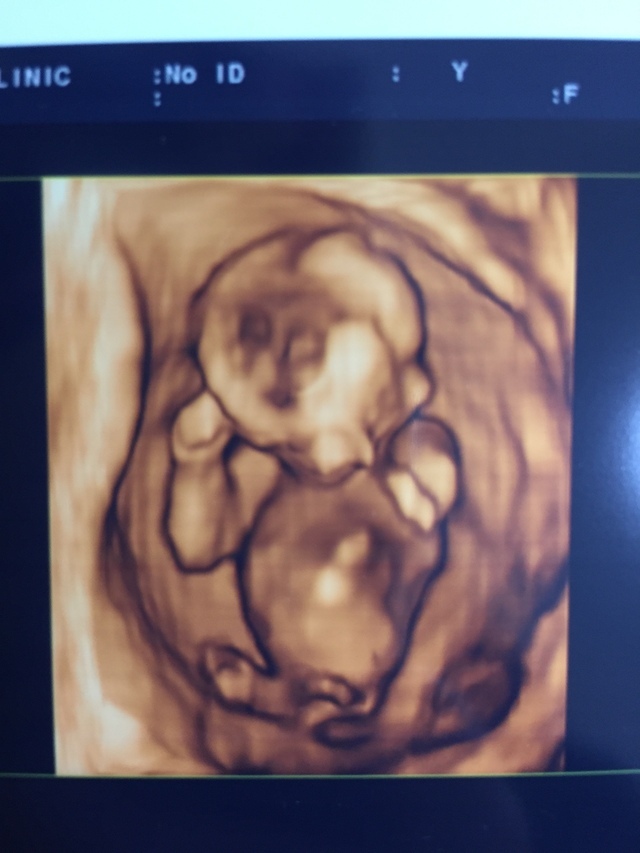

14週2日(14w2d・女の子)|みたらしだんご さん(25歳)

エコー写真撮影時のエピソード:

初めての4Dエコーで、先生も説明しながら笑うぐらい元気よく動いていました。 阿波踊りおどってるみたいだねと終始笑いながらの検診になったことをよく覚えています。

旦那も初めて一緒にエコーを見た時だったので、こんな元気な姿を一緒に見れてとてもうれしかったです。